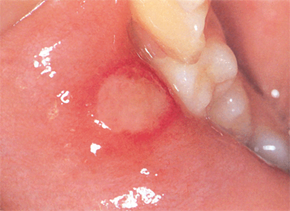

구내염의 가지 수에는 첫 번째로 궤양의 종류인 아프타성 궤양이 있어요. 뺨과 혀, 입술 안쪽에서 생기는 붉은 고리 속 옅은 노란색 궤양의 형태를 보입니다.

재발성 질병인 아프타성 궤양의 원인은 유전성, 많은 면역반응, 염증성 사이토카인의 증가와 관련이 있을 것으로 가설하고 있습니다.

구강 내 자극으로 인한 스크래치가 생겼거나 많은 스트레스와 피로를 최고 많은 사유로 짐작하였으있다고 합니다. 복취하는 식단(커피, 초콜릿, 치즈, 감귤류, 견과류, 감자..)이나 약물, 임신 중 그렇지 아니하면 피임약 복용 중에 발생하기도 하며 금연을 할 때에 나타나는 기회가 잦다고 하고요.

또 비타민B, 철분, 엽산이 부족할 때에도 일으켜서 난다고 합니다.